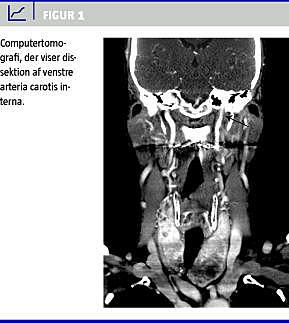

Ved neurologisk tilsyn blev der yderligere fundet venstresidig udglattet nasolabialfure som tegn på nervus facialis-påvirkning. Neurologen mistænkte dissektion af venstre arteria carotis interna eller arteria vertebralis. CT-angiografi viste dissektion af venstre arteria carotis interna, se Figur 1 .